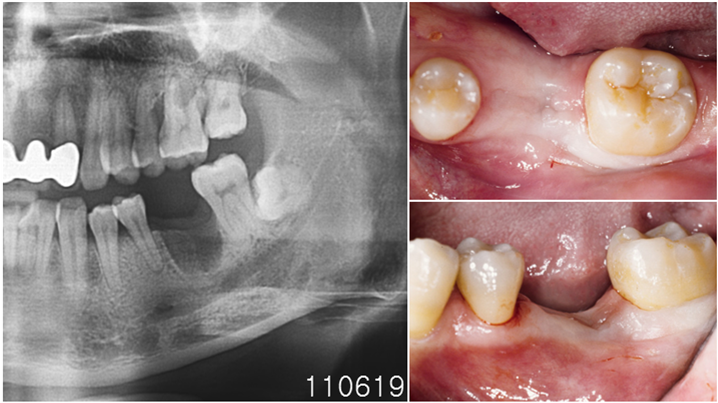

Clinical case: Bone growth in deepest thread of 8.0mm AnyRidge fixture

- Courtesy of Dr. Kwang Bum Park -

Clinical case: Bone filling into the bottom of deepest thread at 8.0mm AnyRidge fixture

Keywords

AnyRidge, Knifethread ,extraction socket, ,initial stability ,Allograft, ,osseointegratio ,Dr. Kwang Bum Park, , Mandibular, Single replacement, AnyRidge, Mega-oss,

Products used

Implant system-AnyRidge, Regeneration-Mega-Oss